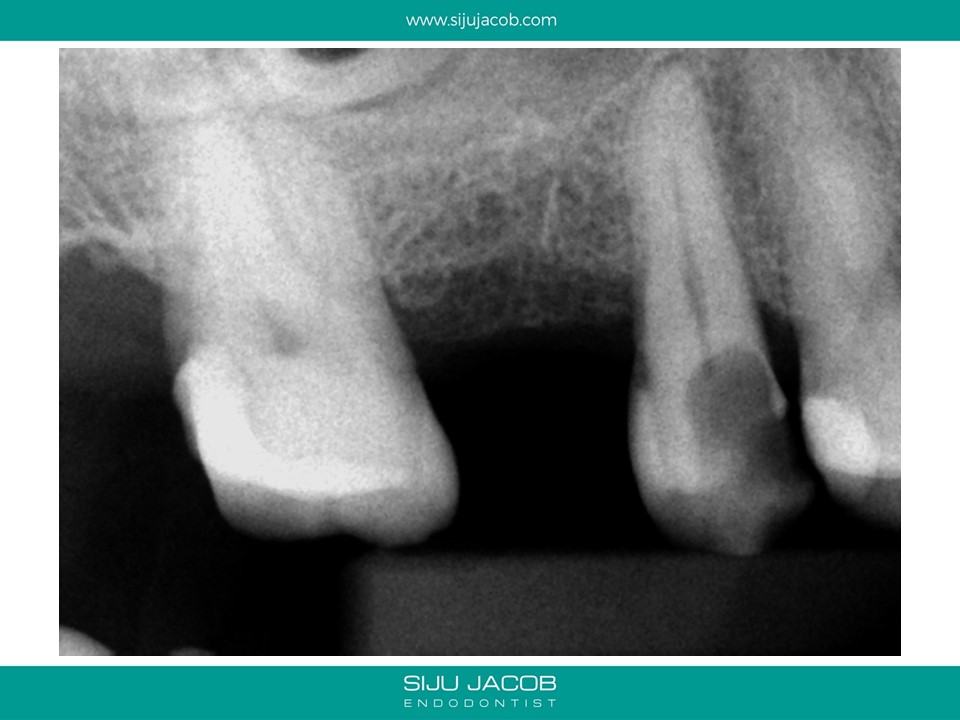

This maxillary premolar bufurcated quite deep into two canals. These type of cases are good examples of anatomy that can easily be missed without magnification.